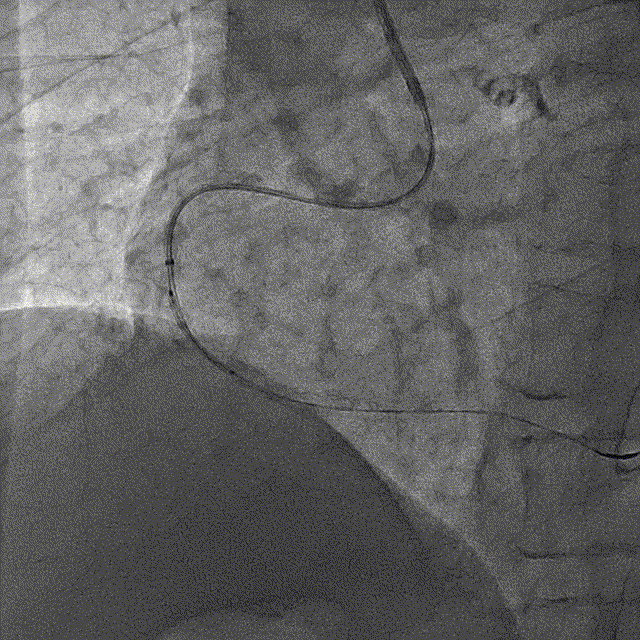

冠脉造影结果:LM外膜钙化,内膜不光滑,中段狭窄90%,TIMI3级。LCX外膜钙化,内膜不光滑,TIMI3级。RCA外膜钙化,内膜不光滑,近段狭窄80%,中段狭窄90%,可见破损斑块,TIMI3级。

冠脉内介入治疗